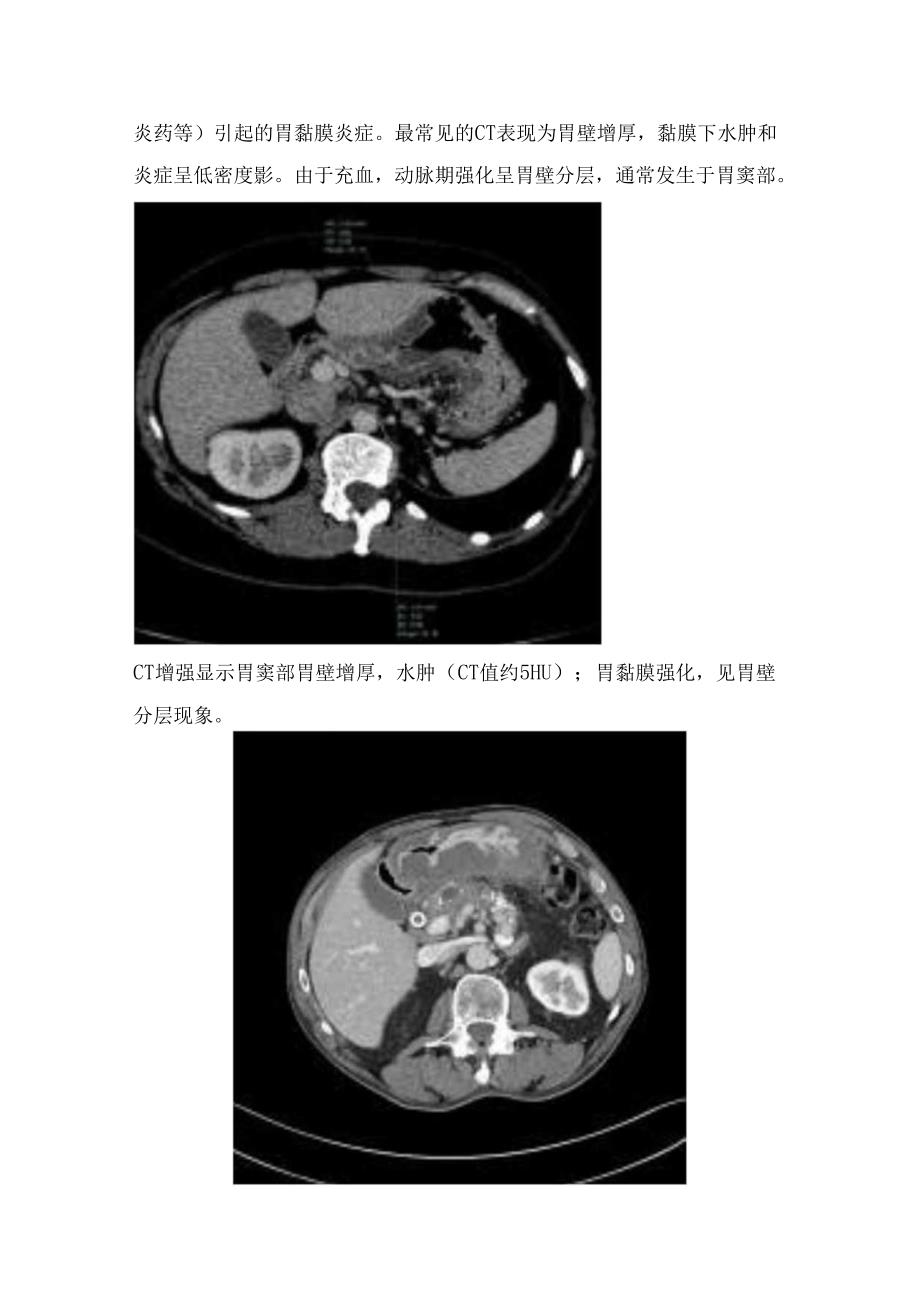

2、病变胃炎(gastritis)是各种原因(酒精、幽门螺杆菌、非留体抗炎药等)引起的胃黏膜炎症。最常见的CT表现为胃壁增厚,黏膜下水肿和炎症呈低密度影。由于充血,动脉期强化呈胃壁分层,通常发生于胃窦部。CT增强显示胃窦部胃壁增厚,水肿(CT值约5HU);胃黏膜强化,见胃壁分层现象。CT增强显示:胃体及胃窦部胃壁明显增厚、水肿,增强后呈胃壁分层。气肿性胃炎(emphysematousgastritis)是一种罕见的由产气细菌在胃壁内繁殖所致的胃壁含气性蜂窝组织炎。早期患者很少表现出临床症状,患者可出现严重疼痛,并可能伴有败血症和休克。CT表现包括胃炎的特征,如胃壁增厚和水肿,并伴有壁内气体,这些气